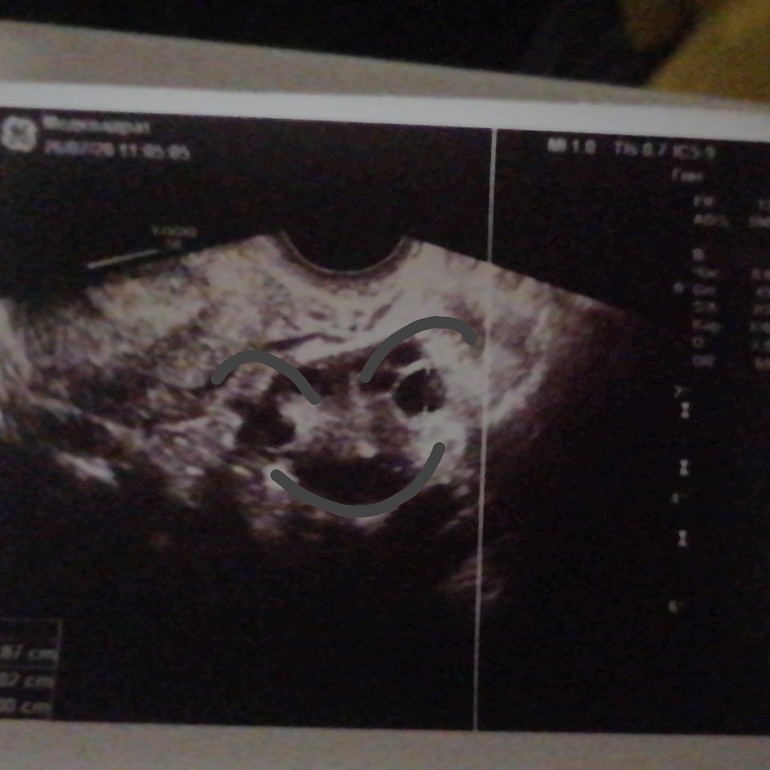

Девочки, кто разбирается, это может быть дф или просто темнота снимка?

"улыбка" на верхнем снимке. Или это посто темнота какая-то вокруг яичника?

Вот тут, "улыбка" этого чудища

ДФ правильной формы, улыбка явно не относится к ней.